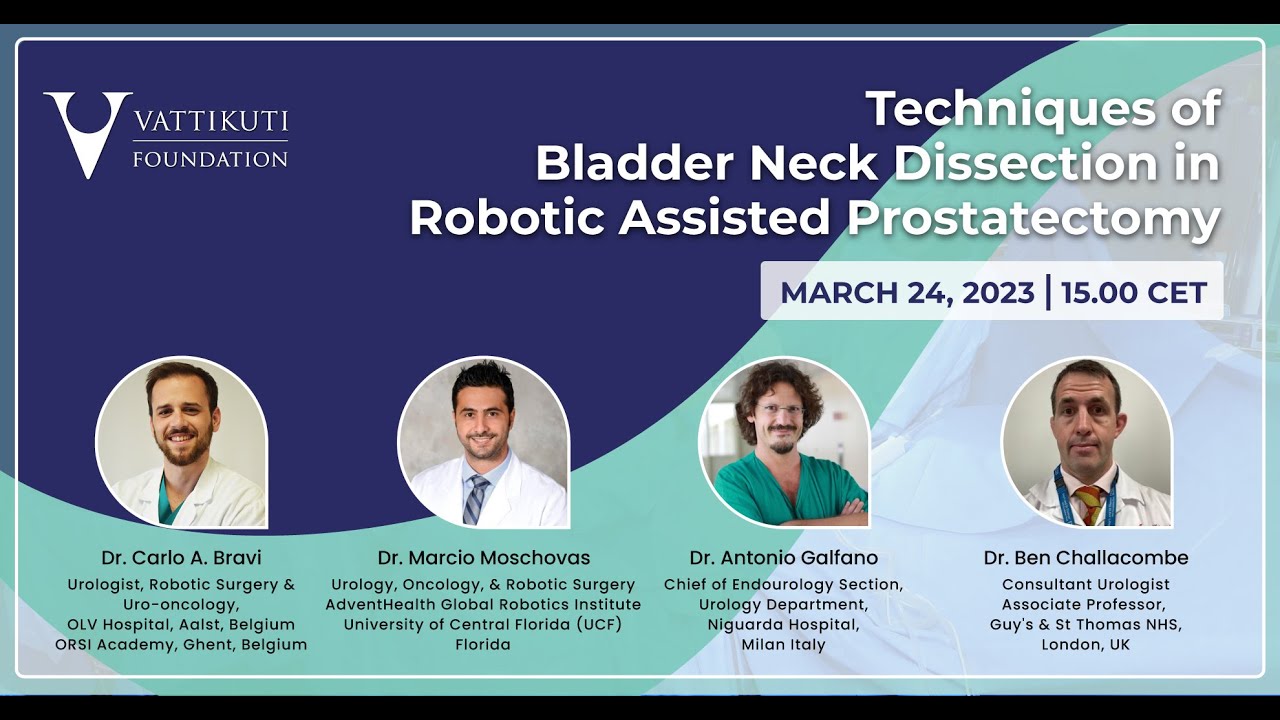

Techniques of Bladder Neck Dissection in Robotic Assisted Prostatectomy

Masterclass, Oncology, Robotics, Urology ';